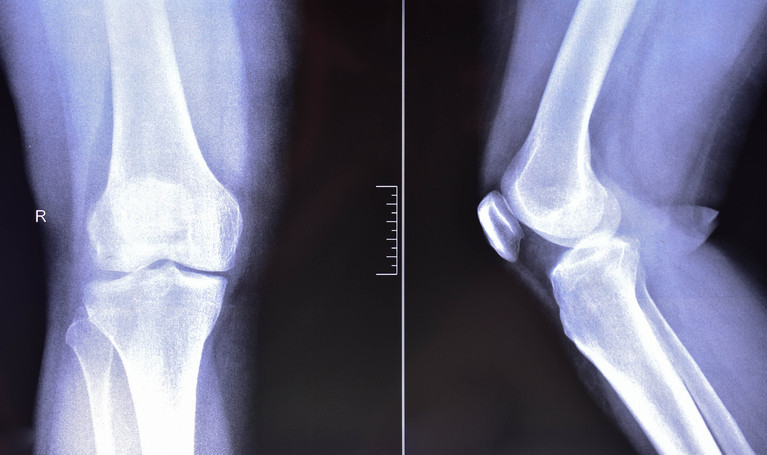

Doktorlar, motosiklet kazalarında ayak bileği, diz ve kalça etrafında önemli kırıklarla sıkça karşılaştıklarını belirtiyor.

Aşırı sürat nedeniyle hastalar önemli travmalarla geliyor. Birçok genç olan şoförlerde ayak bileği, diz ve kalça etrafında kesimli ve eklem içi kırıklarla karşılaşılıyor.

Bazı kırıklar uzun vadeli sakatlık riski taşıyor. Kalça yuvasının kırılıp femur başının yuvadan çıktığı asetabulum kırıklarıyla sık karşılaşıyoruz. Bu kırıkların tedavisi hayli güç.

Eklem içi kırıklarda ilerleyen yıllarda hareket kısıtlılığı ve kalıcı sakatlıklar görülebiliyor. Genç yaşta yaşanan bu kazalar, hastalarımızın hem iş hem de toplumsal hayatını önemli halde etkiliyor.